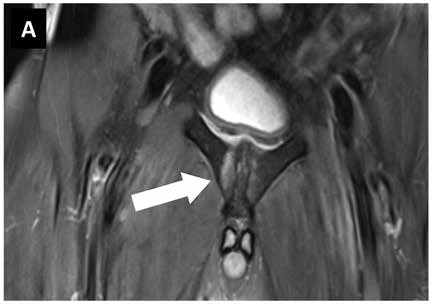

Images: MRI pubic bone branch football player 1st German Bundesliga. (A) Findings before start of therapy with focused ESWT, (B) findings 6 weeks later with no pain under stress.

Images courtesy of sportärztezeitung.